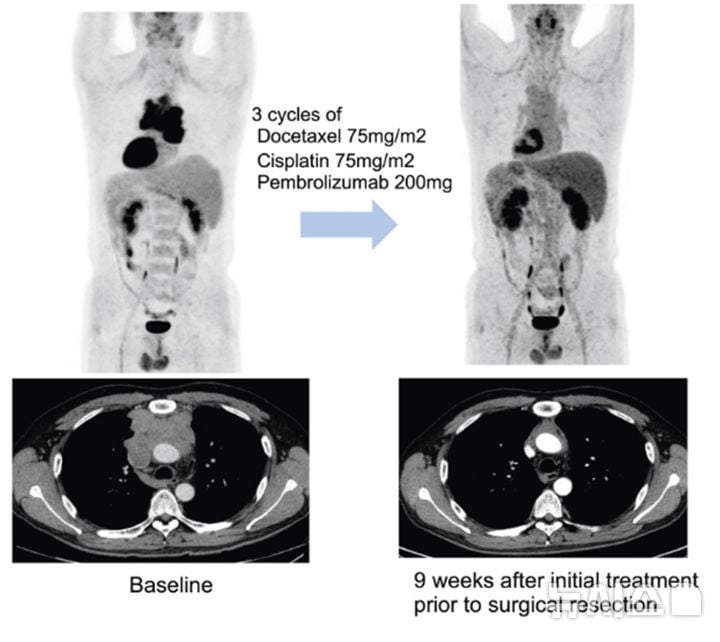

펨브롤리주맙은 항암 면역치료제로서 종양세포의 면역 회피 기전을 저해해 T세포의 암세포 공격을 촉진하는 약물이다. 연구팀은 3주 간격으로 세 차례 기존 항암치료와 병용, 이후 수술 가능성을 재평가했다. 수술 후에는 최대 32주간 펨브롤리주맙을 유지 투약하고, 일부 환자는 항암방사선 치료까지 추가했다. 기존 화학요법만 사용할 경우 치료 반응율이 20~30%에 불과했던 데 비해, 본 연구에서 전체 환자의 57.5%는 종양 크기가 의미 있게 감소했다. 질병의 진행 억제(질병조절률)는 82.5%에 달했다. 수술 자체가 불가능한 환자의 70%가 치료 후 수술이 가능해졌으며, 병리학적 주요 반응(MPR) 도달률도 수술 환자군에서 46.4%로 높았다.

특히 예후가 나쁜 흉선암 환자(전체의 72.5%)에서 반응률이 높았다는 점이 두드러진다. 치료 후 1년 무진행 생존율(DFS)은 87.9%로 기록됐고, 중앙값 무진행 생존 기간은 49.3개월로 장기간 재발 없이 생존하는 환자가 다수를 차지했다. 아직 전체 생존율(OS)의 중앙값에 미치지 않아 장기 생존 가능성이 더욱 커졌다는 평가다.